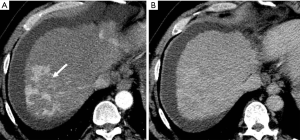

Because HCC remains amongst the most significant long-term sequelae of the cirrhotic liver, small HAPS when observed must carefully be distinguished from de novo HCC. The differentiation between HCC and HAPS is a critical clinical issue requiring a vigilant approach.

The major differentiating imaging features between HAPS and HCC are as follows: (I) a HAPS usually exhibits a peripheral location with a wedge-shaped appearance, straight margin, and cone-shape on three-dimensional reconstructed images. Normal vessels can be seen coursing through the area. (II) “Washout” is regarded as diagnostic for the differentiation of hypervascular HCC from non-tumorous HAPS. The equilibrium phase is also extremely useful in this differentiation as HCC usually arise as an area of heterogeneous low attenuation (or intensity), while the signal attenuation of a HAPS not arising with an HCC will not decrease below parenchymal background (Figure 16). (III) Repeat follow-up imaging procedures usually demonstrate the resolution or stability of a HAPS, as opposed to growth of an HCC.